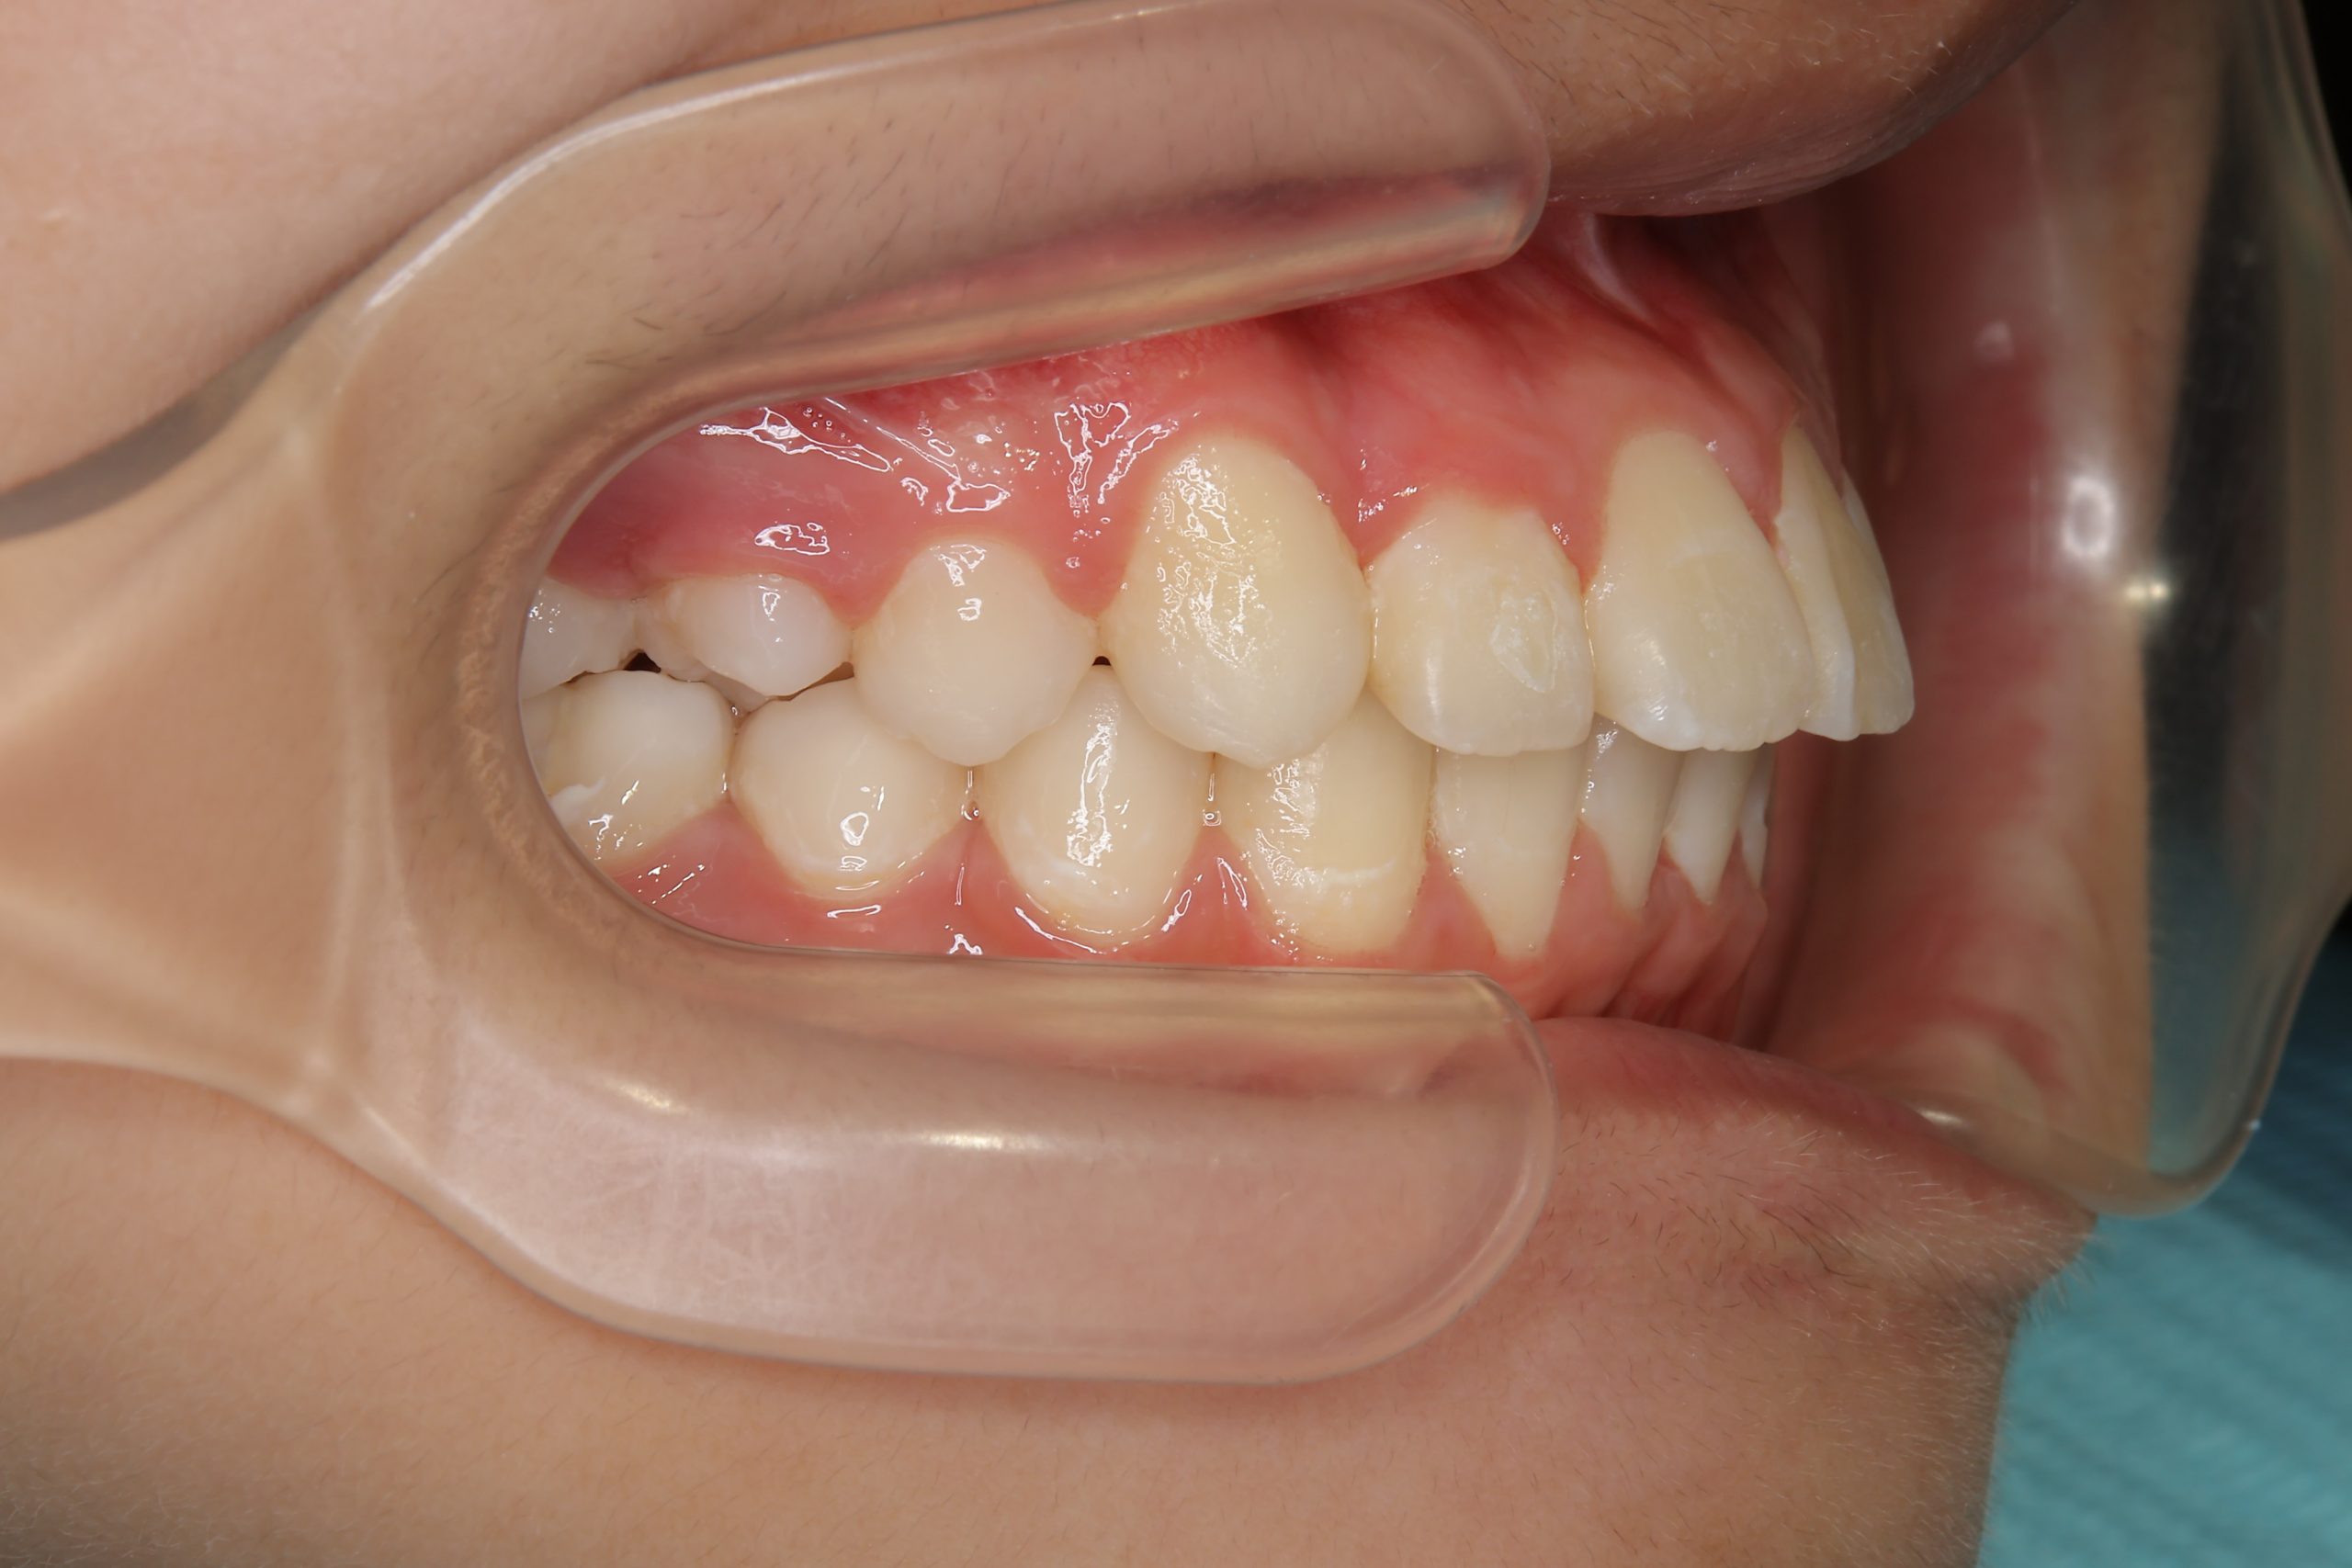

アフター

ワイヤー矯正治療|症例_1324

施術内容 MSEと下顎リンガルアーチを用いて上下顎骨を拡大した。

その後マルチブラケット装置を用いて非抜歯で歯牙を配列し、良好な咬合を獲得した。

治癒期間 1年5か月間